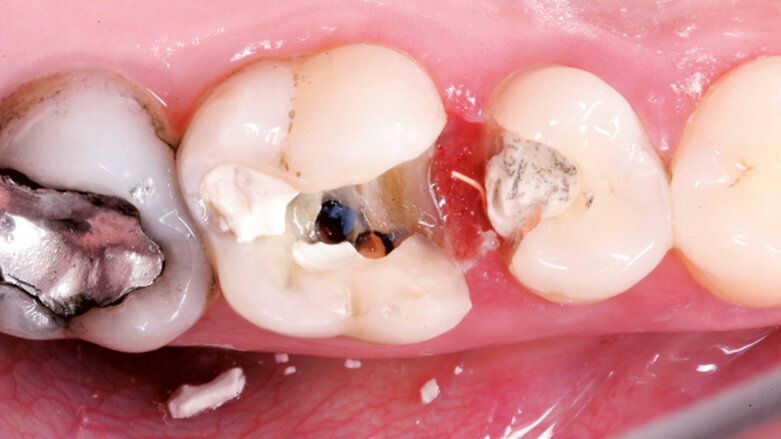

U pacienta v 10 letech byla pro úrazovou ztrátu vitality provedena revaskularizace na zubu 22. Po 2týdenní aplikaci kombinace antibiotik do prostoru pouze chemicky dekontaminovaného kořene byl po vyvolání krvácení aplikován prostředek PRGF a kořen uzavřen pomocí MTA. Zub byl rekonstruován kompozitem. Na kontrole po 5 letech je viditelně zvětšený objem tkáně kořene a absence projasnění. (Obr. 4–6)

Častou komplikací (téměř inherentní součástí) tohoto ošetření je zbarvení korunek ošetřených zubů, které je následně po vytvoření kořenové tkáně nutno řešit vnitřním bělením (obr. 7).